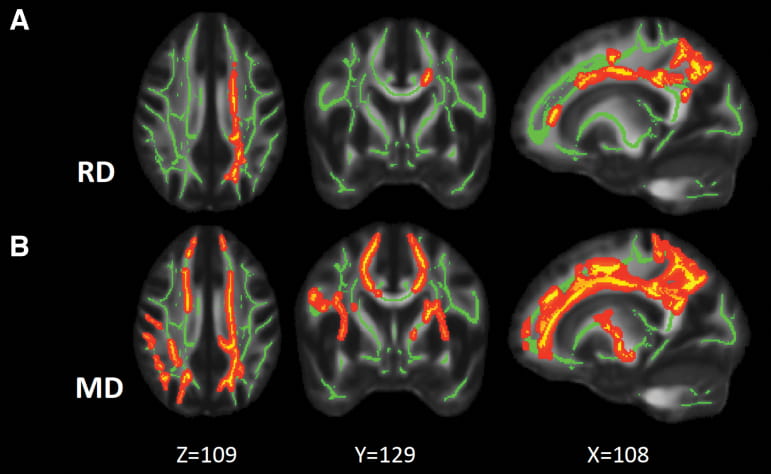

MRI imageThe Advanced Imaging Research group is a joint program between the Stark Neurosciences Research Institute and the Indiana Institute of Biomedical Imaging Sciences at Indiana University School of Medicine. The central mission of the Advanced Imaging Research program is threefold: to advance magnetic resonance imaging (MRI) and positron emission tomography (PET) technologies; to promote working knowledge of MRI and PET physics; and to facilitate integrating advanced imaging technologies into the basic and clinical research community at IU School of Medicine.